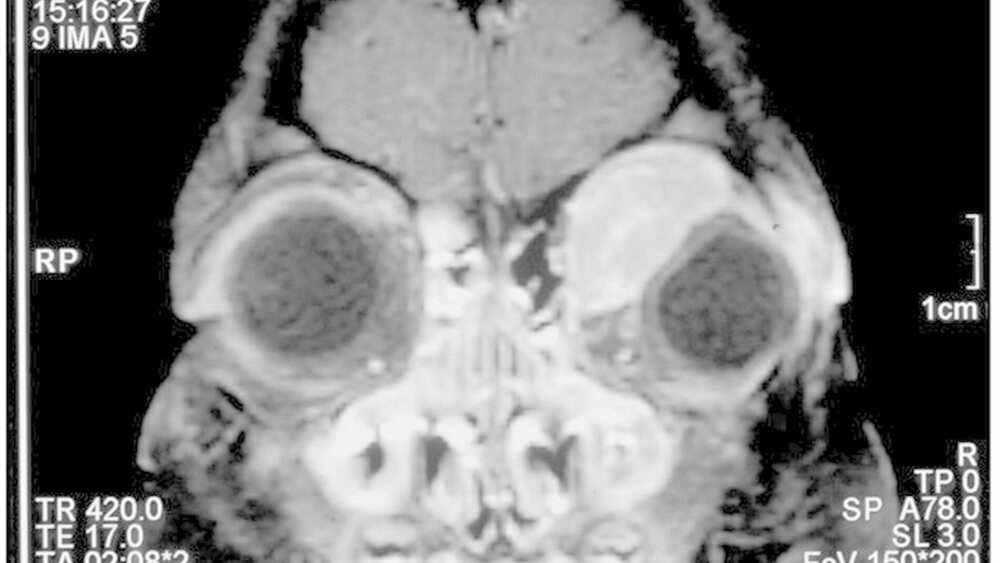

Auf der Jahrestagung der Deutschen Gesellschaft für Mund-, Kiefer- und Gesichtschirurgie (DGMKG) in Essen erzählte die mittlerweile 16-jährige Lisa (Name von der Redaktion geändert) selbst ihre Erfolgsstory: "Als ich fünf Jahre alt war, litt ich an einem seltenen und bösartigen embryonalen Rhabdomyosarkom (hoch bösartiger Weichteiltumor) der linken Augenhöhle. Das MKG-chirurgische Team um Prof. Mohr operierte mich und führte mit besonderen OP-Techniken eine umfangreiche Tumorentfernung durch. Ich bin besonders dankbar, dass ich heute noch lebe, mein Augenlicht erhalten werden konnte und mein Aussehen nicht mehr auf diese Erkrankung hindeutet!"

Beim Rhabdomysarkom handelt es sich um einen extrem bösartigen Weichteiltumor, der von entarteten Zellen der Skelettmuskulatur ausgeht. Er ist mit durchschnittlich 56 Neuerkrankungen pro Jahr der häufigste Weichteiltumor bei Kindern bis zu einem Alter von 15 Jahren. Bei bis zu 14 Kindern pro Jahr liegt der Primärtumor in der Augenhöhle.

Jene weist eine hochkomplexe Anatomie auf engstem Raum auf. Denn dort liegen Augapfel, Sehnerv, Augenmuskeln und Fettgewebe eng beieinander, unmittelbar darüber befindet sich das Gehirn. Daher gehören insbesondere Orbita-Eingriffe in Spezialistenhände.

Im Fall der kleinen Patientin öffneten die Essener MKG-Spezialisten um Prof. Dr. Dr. Christopher Mohr mit einem speziell entwickelten Bügelschnitt vorsichtig die Augenhöhle und entfernten den Tumor so gewebeschonend wie möglich. Denn gerade bei gesichtschirurgischen Eingriffen im Wachstumsalter handelt es sich um eine äußerst schwierige und feinfühlige Chirurgie für ein funktionell und ästhetisch erfolgreiches Ergebnis.

Das Besodnere an dieser Krankengeschichte: Es gelang sogar, die Funktion des Auges vollständig zu erhalten. Nach der Tumorentfernung schloss sich die kinderonkologische Therapie mit Chemotherapieund Bestrahlungen der erweiterten Tumorregion an. Die Verlaufskontrollen beim Augenarzt zeigten keine Bewegungseinschränkung, aber einen Enophthalmus (eingesunkenes Auge) links. Als nächster Schritt folgten dann MGK-chirurgische Korrekturmaßnahmen.